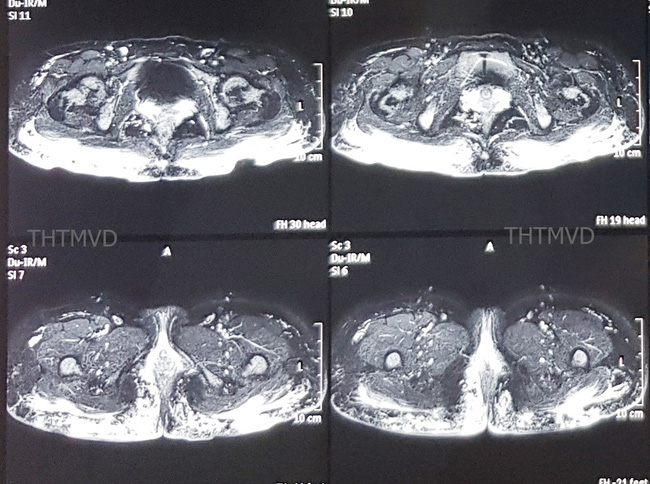

Trên phim chụp cộng hưởng từ MRI 3.0 cho thấy hàng trăm khối u siliconoma cùng hiện tượng viêm lan tỏa trong lớp da cơ mông và thâm nhiễm cả đến gần hậu môn.

PGS.TS Nguyễn Hồng Hà, Trưởng khoa Phẫu thuật - Tạo hình - Thẩm mỹ, Bệnh viện Hữu nghị Việt Đức cho biết bệnh nhân vào viện trong tình trạng mệt mỏi, lo lắng, thiếu máu nhẹ, vùng mông có hiện tượng viêm sưng nề nhiều xen kẽ các vết thủng loét đã vỡ dò chảy mủ ra ngoài. Trên phim chụp cộng hưởng từ MRI 3.0 cho thấy hàng trăm khối u siliconoma cùng hiện tượng viêm lan tỏa trong lớp da cơ mông và thâm nhiễm cả đến gần hậu môn.

Phim cộng hưởng từ cho thấy viêm tấy lan tỏa